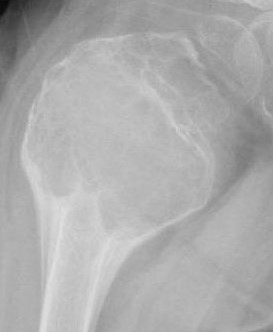

Il secondo caso riguarda Asia, anche lei ha 3 anni e presenta una zoppia. L’esame radiologico iniziale evidenziava la presenza di “una lesione osteolitica multiloculata alla metafisi prossimale femorale”, in relazione della quale erano state eseguite due aspirazioni di materiale sieroso. Dopo 4 mesi, in corrispondenza della sede della lesione radiologica, compare una tumefazione (4x3 cm) non iperemica e non calda al tatto, con dolore localizzato presente anche la notte, tale da risvegliarla. Agli esami ematici l’unico riscontro fuori norma risulta l’LDH (552 U/l). Esegue quindi RM con mezzo di contrasto, che mostra una lesione compatibile in prima ipotesi con cisti aneurismatica dell’osso (Figura 1). Viene eseguita agobiopsia della lesione che conferma la diagnosi con l’istologia.

La cisti ossea aneurismatica è una lesione reattiva dell’osso (circa 1% dei tumori ossei benigni) caratterizzata da lacune ematiche separate da setti di tessuto mesenchimale con occasionali trabecole ossee. Colpisce più frequentemente la prima decade, e si presenta più spesso a livello delle metafisi delle ossa lunghe. Il suo trattamento prevede la chirurgia con curettage o in alternativa l’embolizzazione arteriosa e iniezione di agenti sclerotizzanti.